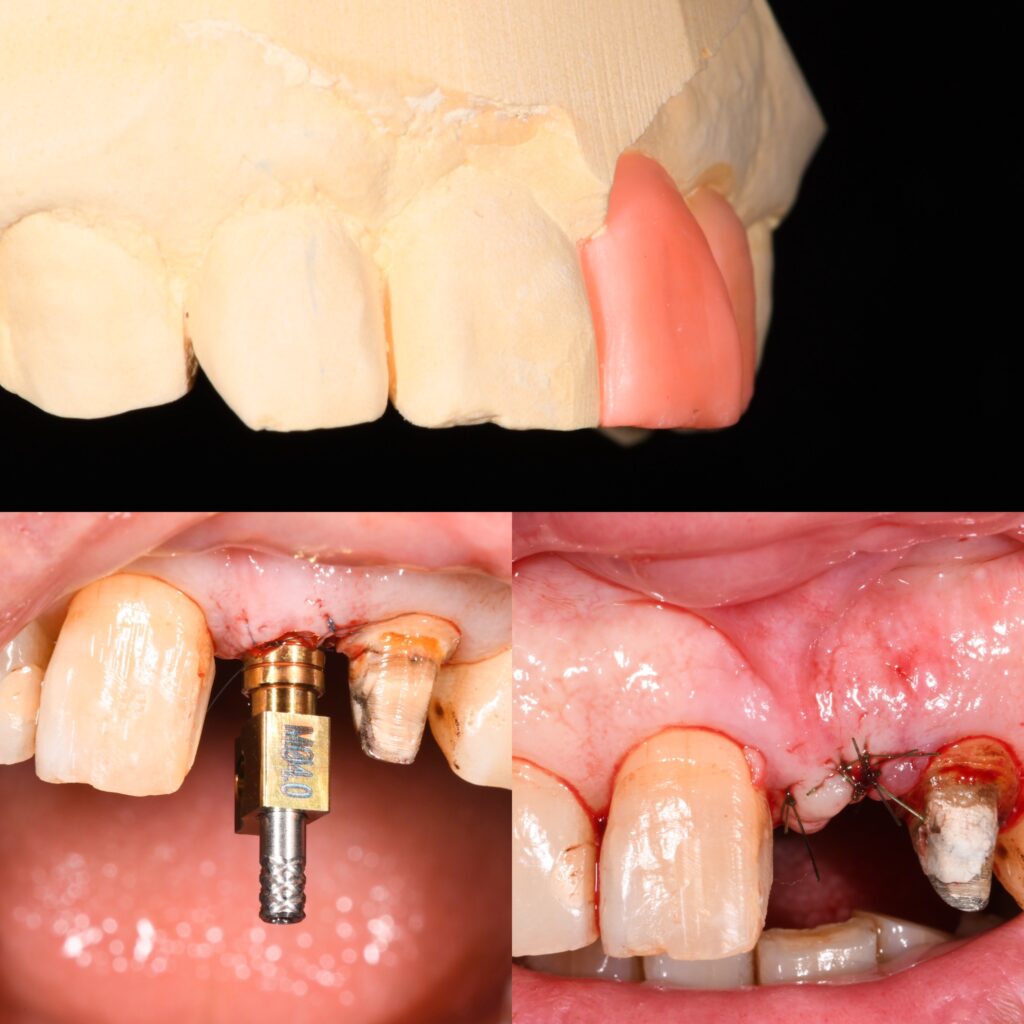

インプラントとは、失った歯の代わりに人工の歯根を顎の骨に埋め込み、その上に人工の歯を装着する治療法です。従来の義歯やブリッジと比べて、自然な見た目と機能を取り戻すことができるため、非常に人気があります。インプラントはチタン製のスクリューを使用し、顎の骨と結合することで安定性を確保します。この結合をオッセオインテグレーションと呼び、インプラントの成功には欠かせないプロセスです。